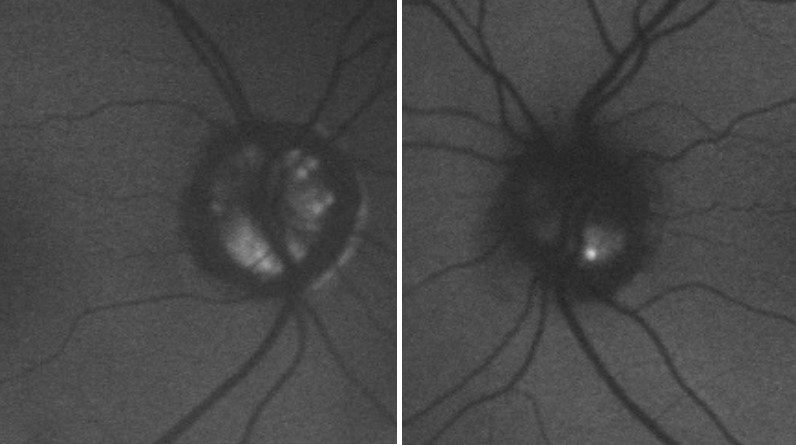

At presentation, her best-corrected visual acuity was 6/6 in either eye, colour vision was normal and she had normal pupil reactions. IOP was 14mmHg in each eye on applanation tonometry and her central corneal thickness measured 491um and 498um in right and left eyes respectively. Anterior segment examination was unremarkable and she had open drainage angles on gonioscopy. Dilated fundus examination showed bilateral ONHD (Figure 1),

which were confirmed by fundus autofluorescence and B scan ultrasonography(Figure 2).(Figure 3) The optic discs were not abnormally excavated and no localised retinal nerve fibre layer (RNFL) defects were visible, however there was some inferior beta zone peripapillary atrophy in both eyes. Standard automated perimetry (SAP), which was of good reliability, showed significant decreased sensitivity in both eyes but more advanced in the right eye (Figure 4) with a mean deviation (MD) of -15.57 dB in the right eye and -3.13 dB in the left. Due to the disc swelling and marked visual field defects she underwent MRI imaging of her brain and visual pathways, which was normal.

Figure 2.Fundus autofluorescence